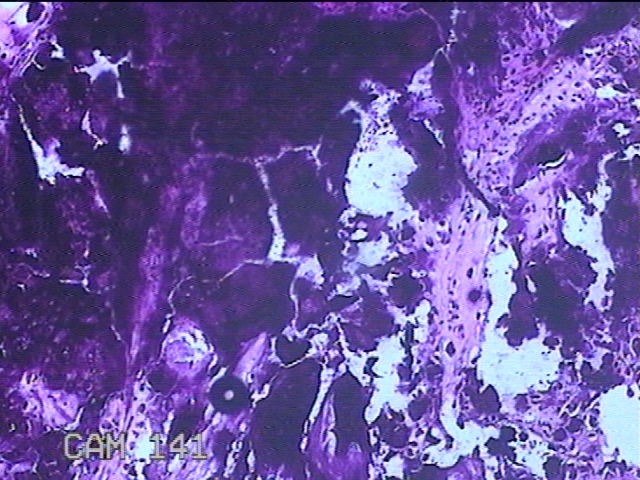

右侧臀部包块

性别

男

年龄

27岁

临床诊断

臀部良性肿瘤

一般病史

发现右侧臀部包块2年余,无明显疼痛及不适。

标本名称

大体所见

灰白暗红色组织2.3x1.7x1.3cm一块,表面带梭形皮肤2x1.3cm,皮下见包块2.3x1.3x1cm一个,切开包块呈实性,切面灰白粉红色,质中。

考虑瘤样钙质沉着,连蒙带猜了。